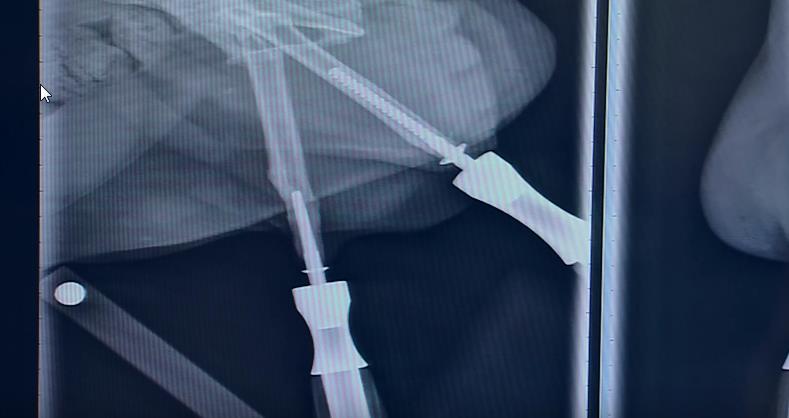

Le Dr. Mary Sarah Bergh, un professeur de l’institut de chirurgie de l’université vétérinaire de Lloyd (Iowa, USA), s’est associée à la société Biomedtrix afin de créer une prothèse de pattes en titane, permettant ainsi au gentil bipède estropié d’enfin de déplacer comme à peu près tous les félins.

Ces prothèses doivent, par contre, être implantées de manière chirurgicale afin d’être intégrées au bassin de l’animal. Regardez le résultat en images, il semble plutôt heureux de cette avancée technologique !